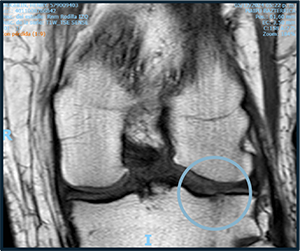

PRE-TREATMENT

NOVEMBER 2023

POST-TREATMENT

NOVEMBER 2024